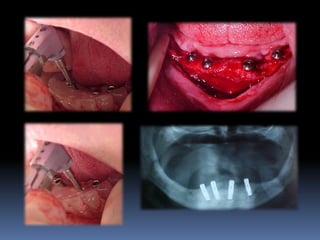

Atrofias ósseas

•Procedimentos de enxertia óssea para

restabelecimento de dimensões perdidas

•Compensações dos tecidos perdidos nas

próteses

Perdas ósseas posteriores – levantamento de seio maxilar

Mathias MA

Sinus lift